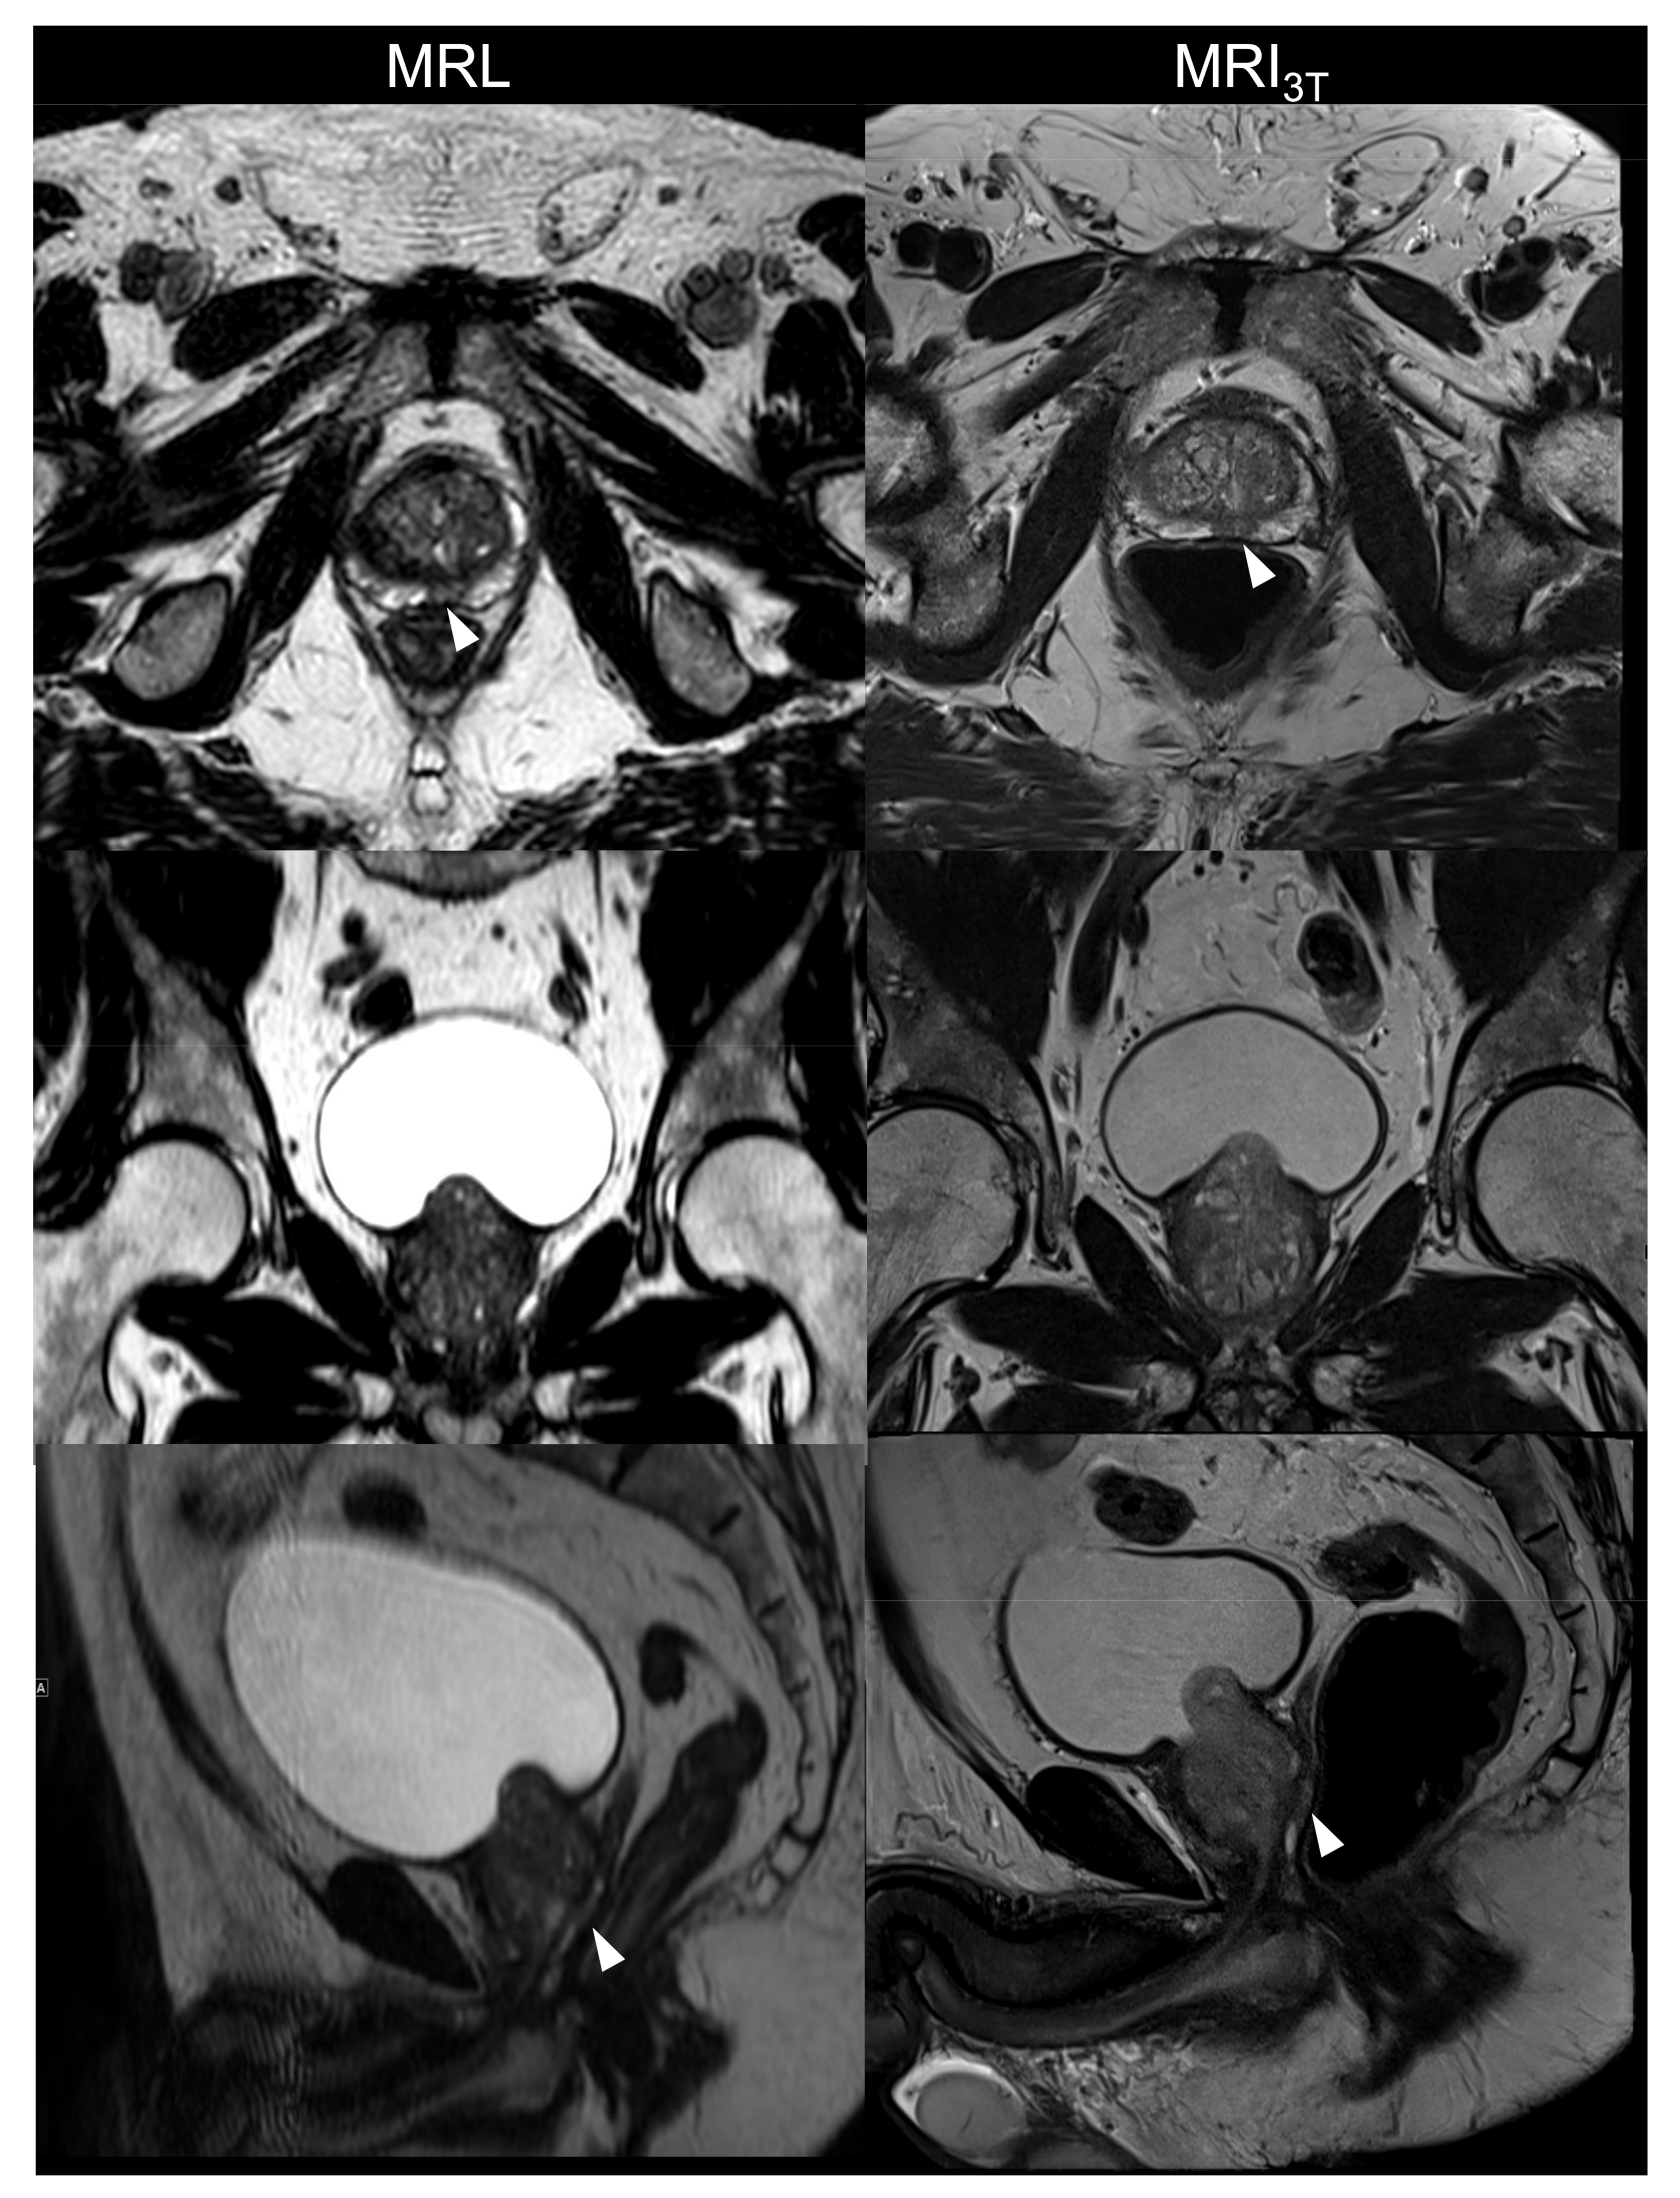

3.1.1. Image Quality

3.1.2. Lesion Conspicuity and Diagnostic Confidence on MRL Alone and in Consensus with MRI3T